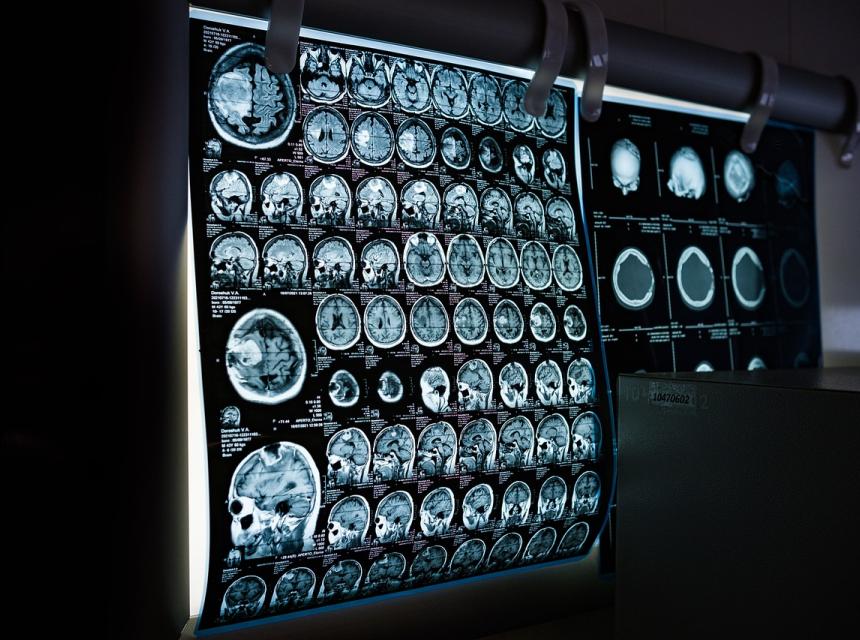

Pokusím se stručně popsat můj příběh. V prosinci loňského roku mi lékaři řekli, že mám zhoubný nádor v hlavě, velikosti 11cm. Dělali mi dvě vyšetření, protože se jim v laboratoři nejdříve pomíchaly výsledky. Na začátku ledna mi nabídli chemoterapii. Odmítla jsem to s tím, že bych chtěla zkusit jinou, přírodnější léčbu. Doktor mně z ordinace skoro vyhodil, že se nebude podílet na mé smrti. Milý doktor, že? No a pak mi jeden známý doporučil MMS, ať to zkusím. V tu chvíli jsem byla rozhodnutá zkusit všechno, abych to překonala. Na začátku jsme měla tendenci se litovat, ale začala jsem užívat osm kapek každou hodinu osm hodin denně. MMS jsem aktivovala kyselinou citronovou. Celé dva měsíce jsem neustále zvracela a první měsíc jsem k tomu měla průjem, ale když jsem přišla na kontrolu, po dvou měsících byl nádor o pět cm menší. To mi dodalo sílu k dalšímu boji, protože to bylo fakt hnusné. Pak už to tak rychle nešlo, už jsem nezvracela ani neběhala na toaletu. Při tom všem jsem pořád chodila do práce. Ted, když se na to zpětně dívám, tak nechápu, jak jsem to zvládla. Po dalších čtyřech měsících měl nádor jen necelé dva cm. V tom čase jsme přestala MMS užívat, protože to bylo před odjezdem na dovolenou. Neužívala jsem to tři týdny a pak jsem začala znova, ale už jenom tři kapky každou hodinu měsíc. Pak jsem znova jela na testy a nádor byl pryč. Rakovinové buňky nejsou ani v krvi, k nelibosti doktora. Řekl, že je to neuvěřitelné, a z lékařského hlediska v podstatě nemožné, ale že má výsledky na papíře, takže věřit musí, ale nechápe to. MMS teď neužívám, protože se mi z něj udělal ledvinový kámen, který mi zablokoval ledvinu. Takže jsem skončila na operaci, vytáhli mi ten kámen a teď marodím. Poslali ho na rozbor a je z větší části plný soli.